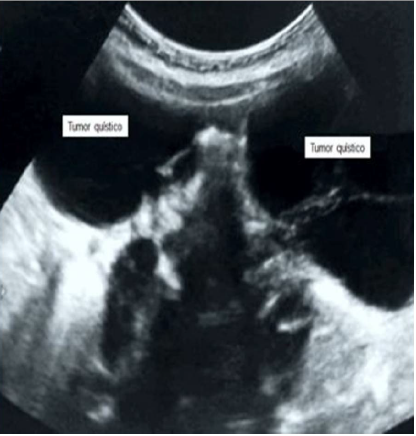

La ecografía pélvica demostró la presencia de tumores quísticos presentes en cada ovario, de paredes lisas, multiloculares, ecos internos gruesos y ausencia de porciones sólidas. El del ovario derecho medía 6 x 5 centímetros y el del izquierdo media 9 x 6 centímetros, con un volumen combinado de 257 mm. y puntuación de Sassone de 6 puntos (figura 1). El útero de aspecto normal, medía 3,2 × 2,0 centímetros con endometrio hiperecoico e intacto (figura 2). No se observaron otras patologías abdominales o pélvicas. La determinación de la edad ósea de la paciente era comparable a la de sujetos femeninos de 32 meses según la puntuación de Greulich-Pyle, por lo que fue considerada como normal. Las imágenes de resonancia magnética cerebral no mostraron lesiones o tumoraciones. En vista de los hallazgos se realizó el diagnóstico de pseudo-pubertad precoz debida a quistes foliculares ováricos autónomos bilaterales.